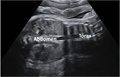

Ecografía del tercer trimestre: Feto de 37 semanas

Vemos abdomen y tórax desproporcionados

Ecografía de un feto de 37 semanas con una desproporción entre el tamaño del abdomen y el del tórax

Este feto presenta una anomalía esquelética clara, con costillas muy cortas, que no permiten un desarrollo adecuado del tórax y de los pulmones fetales. Muchos de estos bebés mueren al nacer por ser incapaces de respirar.